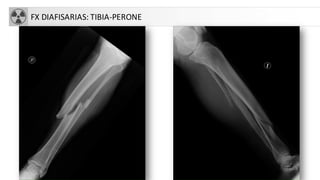

FX DIAFISARIAS: TIBIA-PERONE

• Fx tibia: donde más fracturas abiertas se producen

• Fx peroné